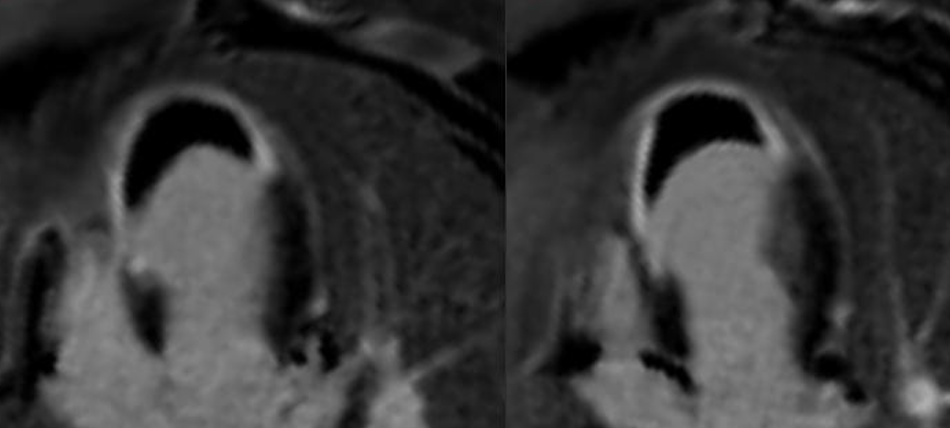

Persistent MVO carries a poor prognosis